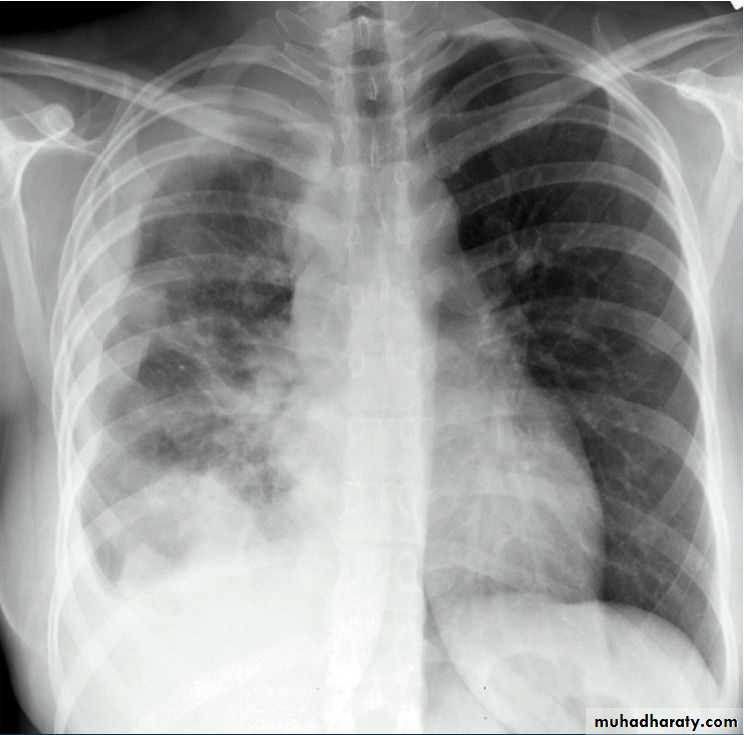

Secondary metastasis

!! ما شرحهم